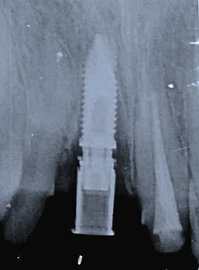

クリスマス日の朝、30代の自営の男性。主訴は「事故で前歯を損傷した。」とのこと。マイクロスコープ等で患部を精査すると差し歯の根が割れていることが判明しました。

抜歯の必要性を伝えたところ、「元々歯並びも悪かったので、前歯3本ともキレイにしたい。抜いた所はインプラントにする。」とのことでした。

お昼休みを使って、緊急手術を始める事になりました。

静脈麻酔鎮静法を使い、浅く眠った状態のまま治療を進めました。

抜歯した痕に自己採血を使って作った再生加工物(CGF)を添加しました。

歯茎を切らず、抜歯した痕に人工的なホールを設け、長さ18㍉のインプラントを移植しました。

また、抜歯した両サイドの2本の歯(1本は神経あり)を削って、オールセラミックの歯を入れる準備も行いました。

これは、抜歯した日にそのままインプラントを移植したところのレントゲン写真です。

無事、仮歯を3本装着して帰って頂きました。